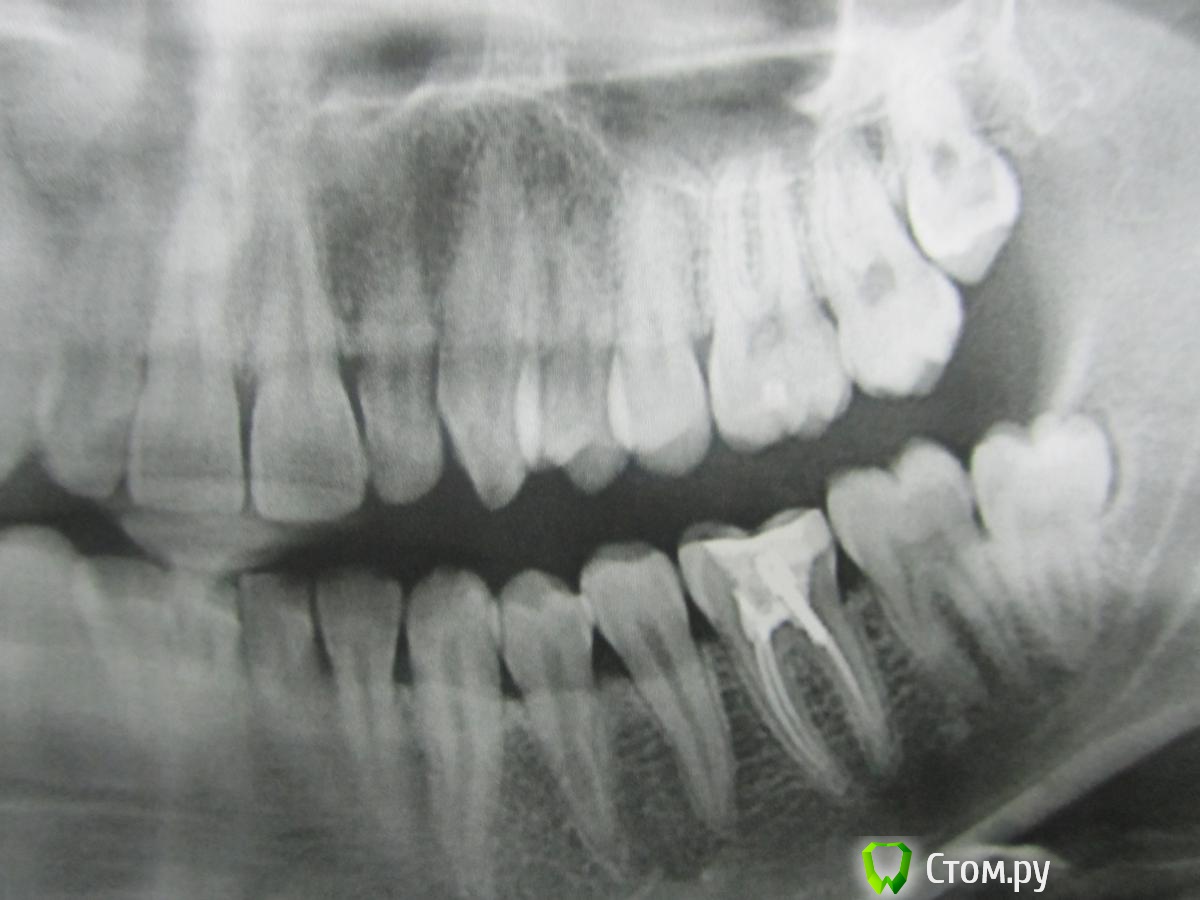

lainux Опубликовано 29 ноября, 2014 Поделиться Опубликовано 29 ноября, 2014 (изменено) Уважаемые врачи, добрый вечер. Два месяца назад установили штифт, зуб периодически стал беспокоит, чувствуется при постукивании по нему небольшая боль. Пошёл к врачу которая делала со снимком, платный кабинет, переделывать отказалась, что её ошибки нет и каналы запломбированы хорошо, сказала попить антибиотики, что продлит неудаление зуба, расстроился нереально. По пути проконсультировался в другой стоматологии, сказали что не долечен канал со штифтом который и надо переделывать, но никак не удалять. Прошу помочь и проконсультировать как быть Изменено 29 ноября, 2014 пользователем lainux Ссылка на комментарий

red_butler Опубликовано 30 ноября, 2014 Поделиться Опубликовано 30 ноября, 2014 то есть который стоматолог делал, тот и должен переделывать?Это Вы решайте сами. Если хотите сохранить зуб, нужен специалист владеющий современными протоколами эндодонтического лечения, работающий с коффердамом и в идеале микроскопом, и после лечения зуб протезировать. Ссылка на комментарий

Shaid Опубликовано 3 декабря, 2014 Поделиться Опубликовано 3 декабря, 2014 Возможно что техническое оснащение клиники(м.б. бюджетная или эконом-класс), в которой был пролечен зуб, не такое высокое.Зуб лучше перелечить(скорее всего, уже в другом месте). нужен специалист владеющий современными протоколами эндодонтического лечения, работающий с коффердамом и в идеале микроскопом +1 Ссылка на комментарий